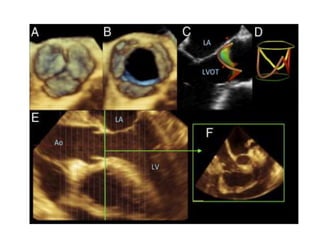

3 DIMENSIONAL ECHOCARDIOGRAPHY

3D Echo of Aortic Stenosis

THREE DIMENSIONAL ECHO/DOPPLER

3D Echo ofAortic Stenosis